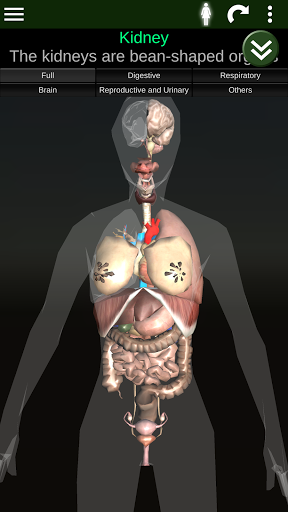

Menampilkan model anatomi 3D dari organ utama tubuh manusia dan penjelasannya masing-masing.

* Mudah diakses dan dinavigasi (zoom, rotasi 3D).

* Deskripsi masing-masing organ.